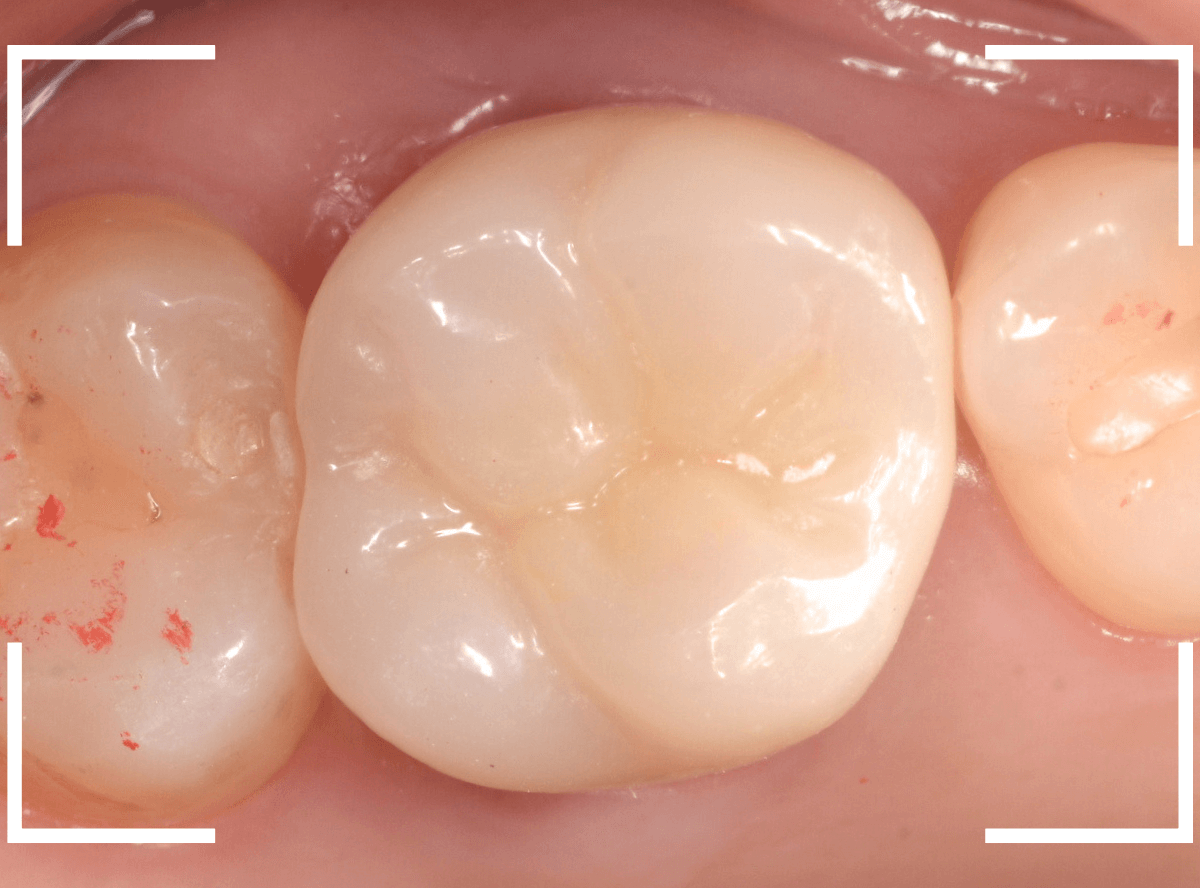

set後の写真です。

患者さんにも満足していただける仕上がりになりました。